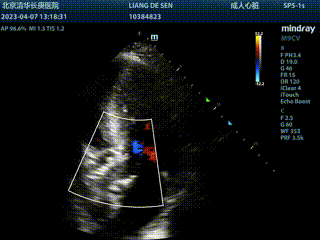

微量瓣周漏

植入后造影微量反流,超声提示瓣膜工作良好,最大跨瓣流速1.7m/s,平均跨瓣压差几乎为0,造影检查主入路,血管未见损伤,手术顺利结束。